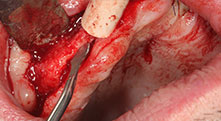

Bratu: Utilizamos los insertos de forma rutinaria para la extracción de injertos óseos y la ranuración de las crestas alveolares. También utilizamos las Piezomed B6/B7 para practicar osteotomías en dientes retenidos y no retiramos implantes que pueden conservarse. Todas estas son indicaciones que requieren cortes profundos y limpios.

Bratu: Preferimos realizar las osteotomías en la línea oblicua externa de la cara posterior del maxilar inferior, y no en la región situada entre los orificios. Tras realizar una incisión en los tejidos blandos, utilizamos las nuevas sierras para definir el contorno de la osteotomía. De este modo, conseguimos una preparación completa en prácticamente el 80 por ciento de los casos. Por otro lado, en algunas ocasiones también utilizamos otros insertos piezoquirúrgicos, así como un cincel para mover el injerto. Para nosotros, esta es una técnica de intervención muy eficaz.